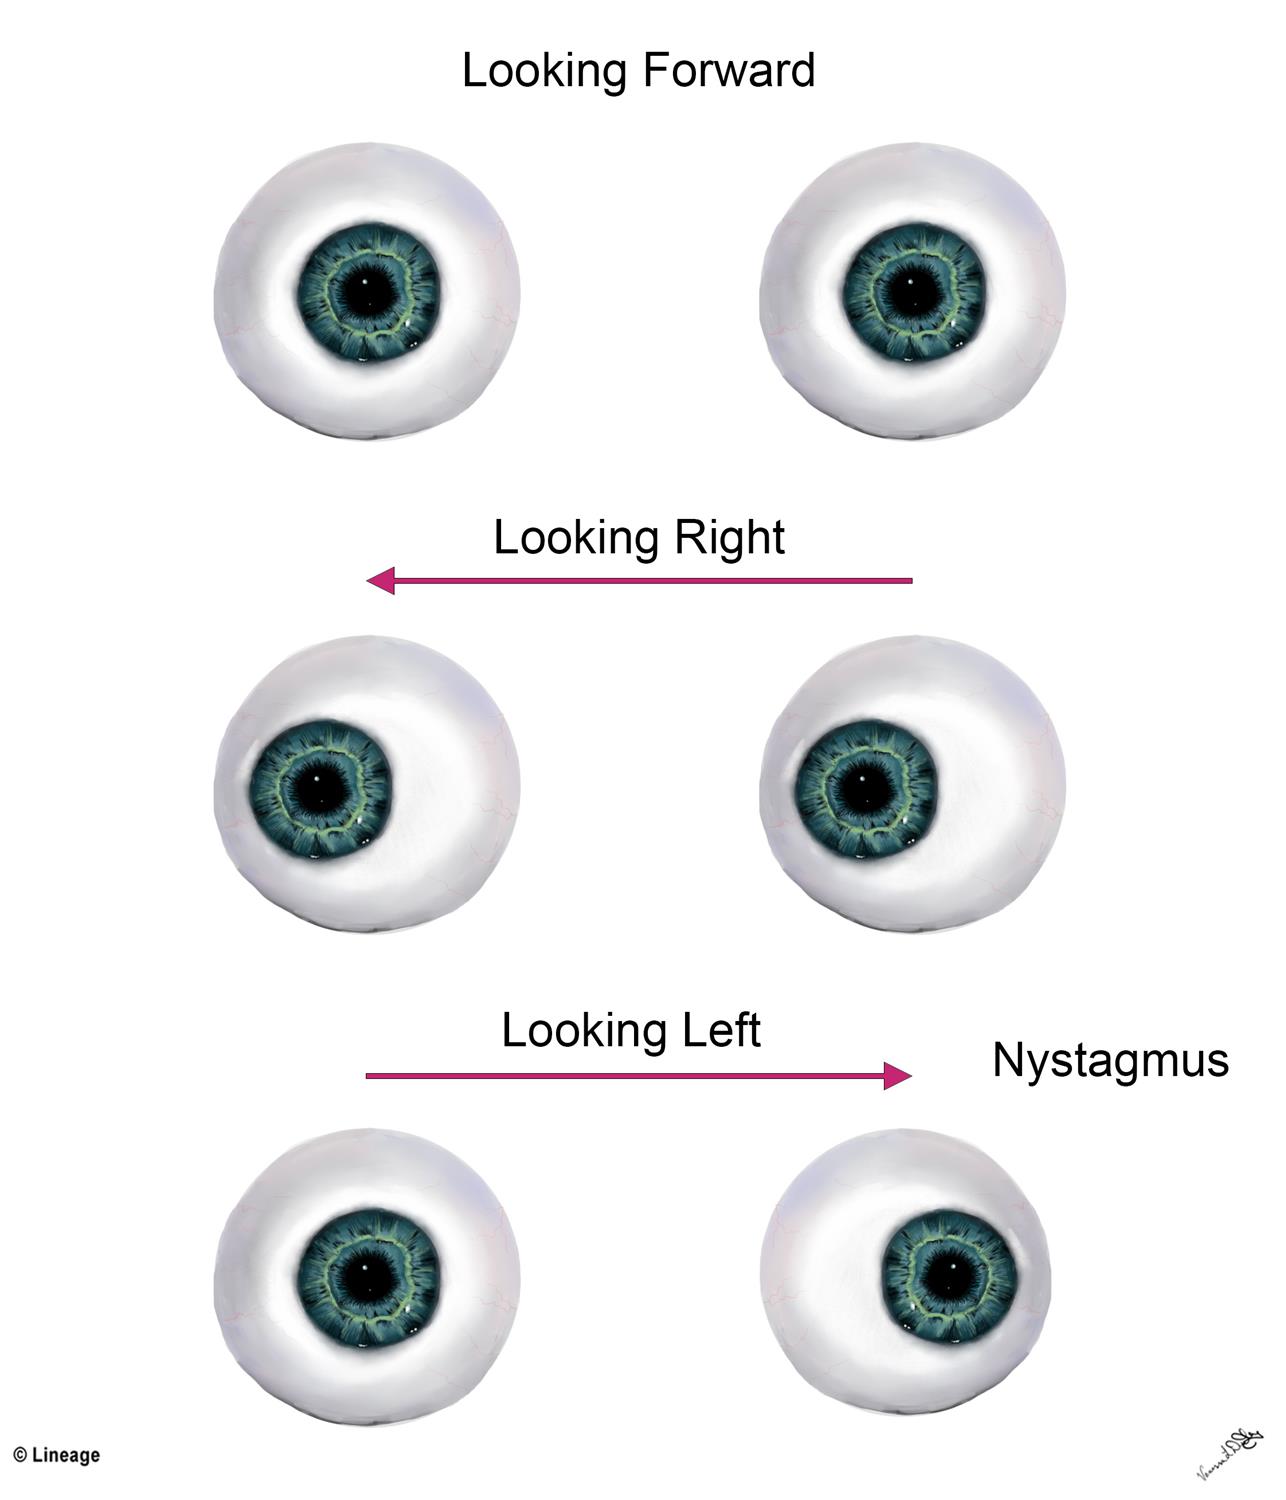

Abduction And Adduction Eyes

ladybird.beauty

ladybird.beauty

An Eye Diagram With The Words Eye Patterns In Blue And White Letters On

www.pinterest.com

www.pinterest.com

Roving Eye Movements